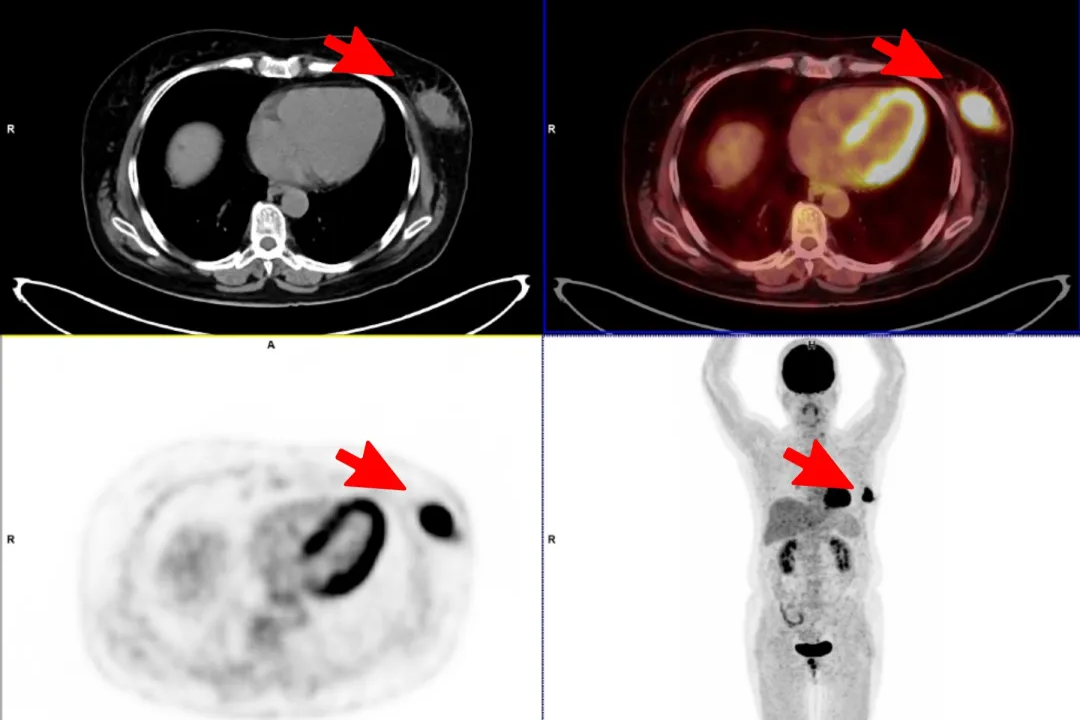

「牵一发而动全身」—以为是肺的事,PET/CT 揭秘—全身淋巴瘤